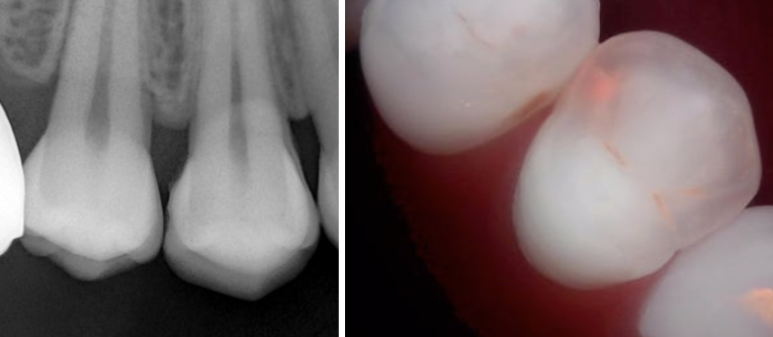

아래 사진은 실제 내원 환자의 예시입니다.

- 겉에서 보면 색 변화 정도만 보여 “충치 맞나요?”라고 물으시지만

- **큐레이(형광 진단기)**로 보면 활성화된 세균 부위가 붉게 빛납니다.

📸 큐레이는

육안이나 엑스레이보다 한발 앞서 충치를 찾아주는 장비로

문정 오늘하루치과의 필수 진단 장비입니다.